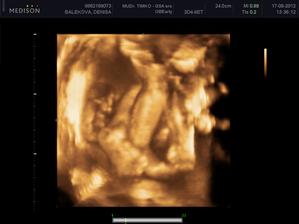

Nas anjelik Alex

Zatial este schovany v brusku ale uz coskoro sa z neho potesime aj nazivo 🙂) Lubime nasho Alexa uz od sameho zaciatku 🙂